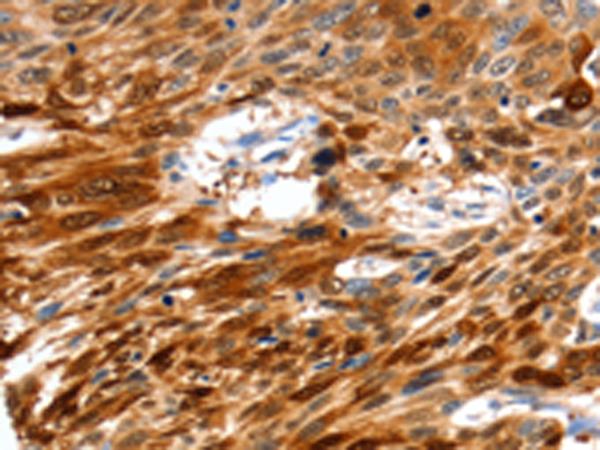

Product Image

The image is immunohistochemistry of paraffin-embedded Human cervical cancer tissue using (NCOR1 Antibody) at dilution 1/60. (Original magnification: ×200)

The image is immunohistochemistry of paraffin-embedded Human esophagus cancer tissue using (NCOR1 Antibody) at dilution 1/60. (Original magnification: ×200)